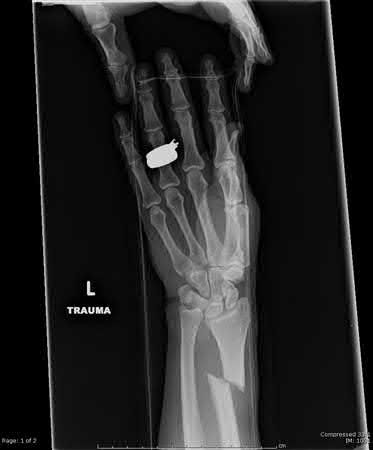

A 38-year-old male suffers the injury shown in Figure A. During operative fixation, free osteoarticular fragments are encountered and reconstruction of these pieces is attempted. Postoperatively, which of the following will have the most beneficial effect on the healing potential of the surviving chondrocytes within these reconstructed articular segments?

Figure A demonstrates a comminuted tibial plateau fracture with significant intra-articular involvement. Basic science evidence has demonstrated that post-operative gentle compressive loading may have a positive impact on articular cartilage healing; however, excessive shear loading may be detrimental.

Irrgang et al provide guidelines for rehabilitation following surgical management of articular cartilage lesions of the knee. They state that after articular cartilage repair, exercises to enhance muscle function must be done in a manner which minimizes shear loading of the joint surfaces in the area of the lesion. The authors also discuss the benefits of gentle compressive loading and motion of the joint, and its positive effects on chondrocyte nutrition.

Furthermore, they recommend a period of protected weight bearing as often being necessary, and that this should be followed by progressive loading of the joint.